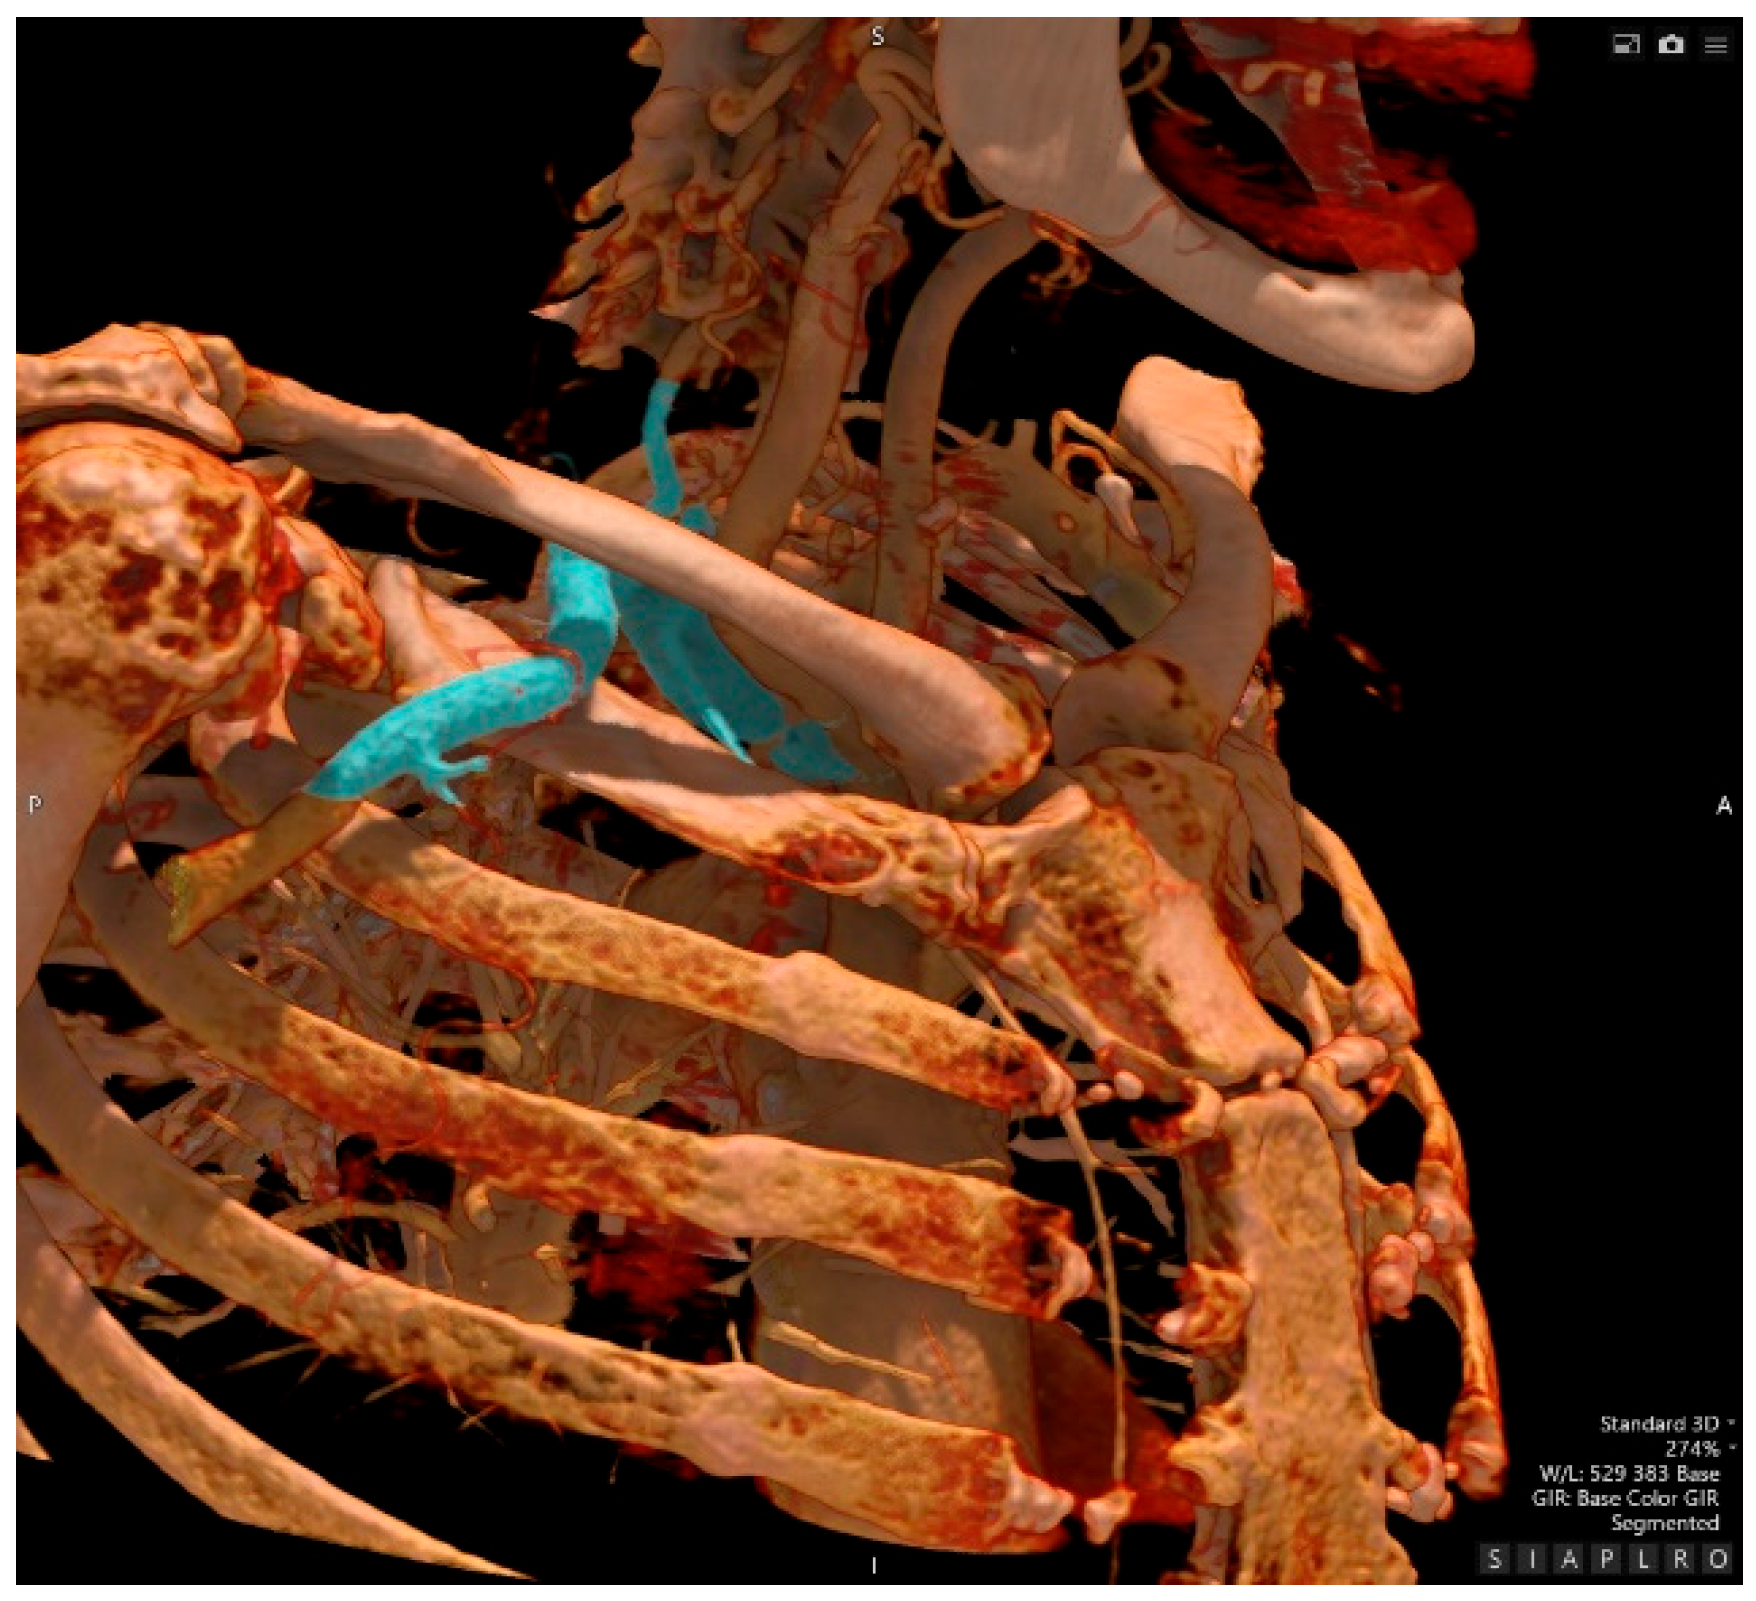

- Computed Tomography Angiography

- Interventional Radiology – an attempt at recanalization of the right subclavian artery